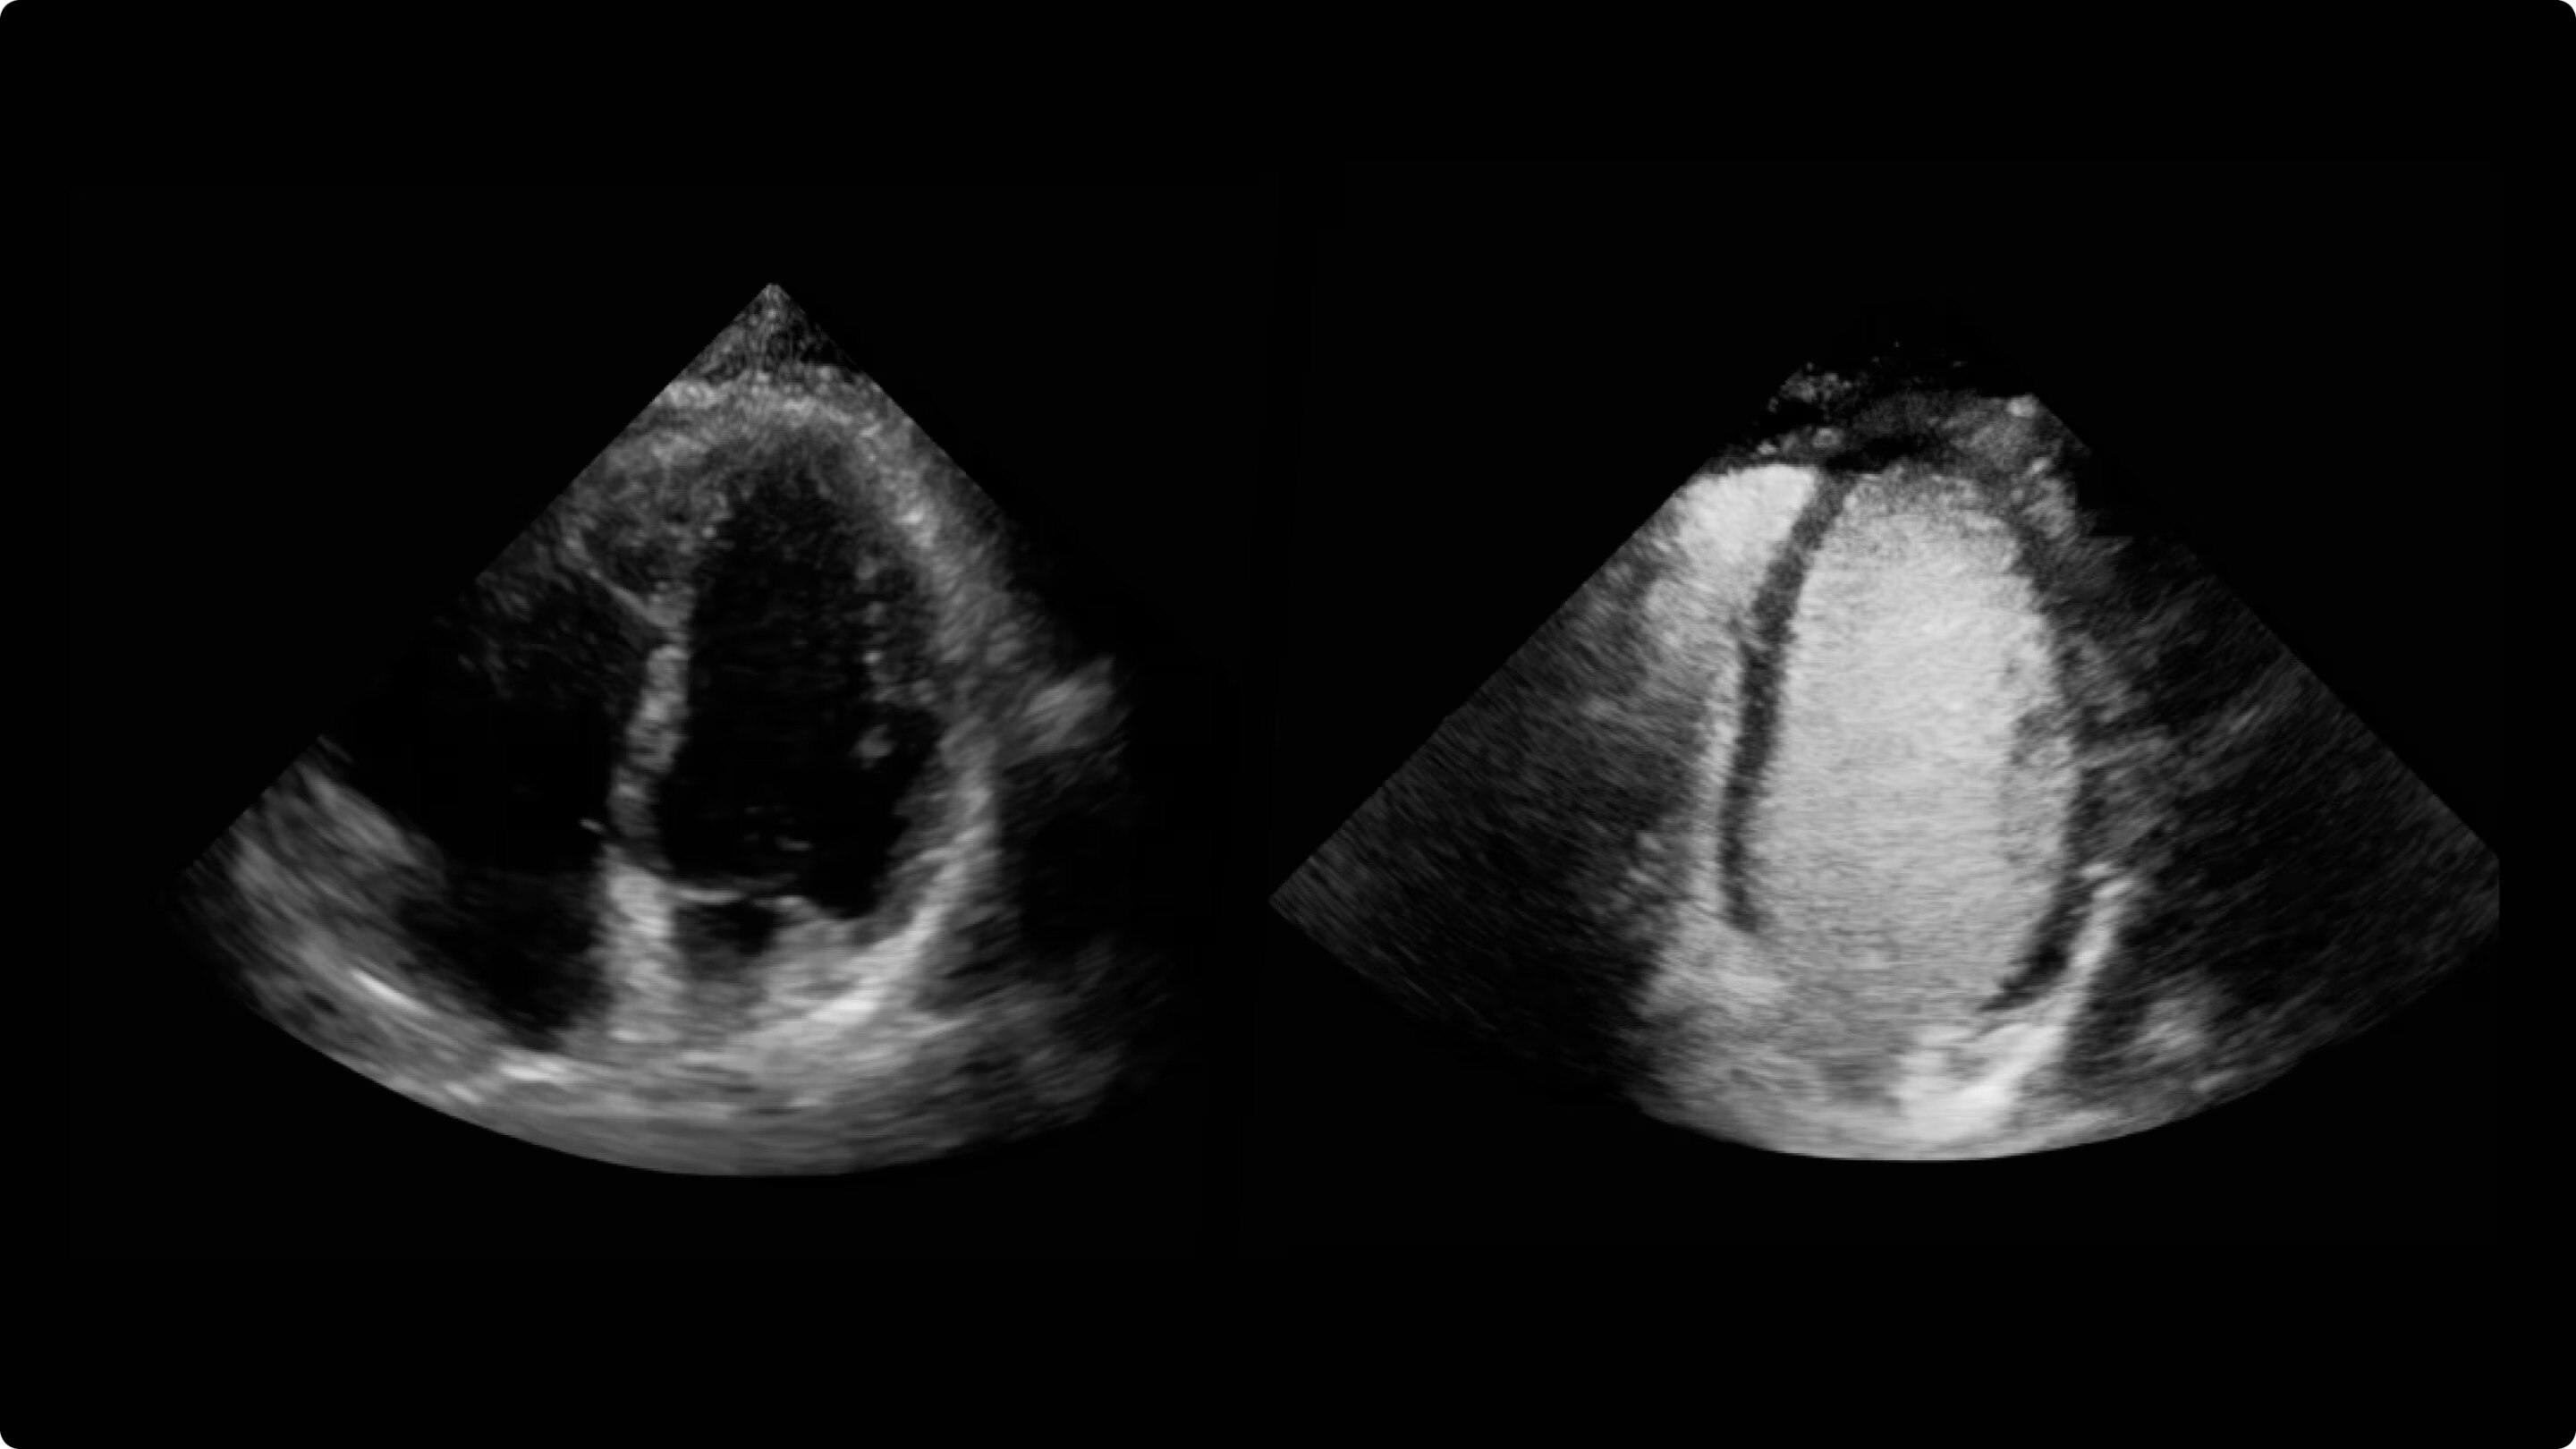

Clear delineation of the endocardial borders may help facilitate evaluation of LV wall motion and function.

a) Images obtained with Vivid™ S70 scanner using Optison.

b) While the products can be used together, Optison and Vivid™ S70 are not Combination Products per 21 CFR 3.2(e); each was FDA-approved independently and neither requires the other.